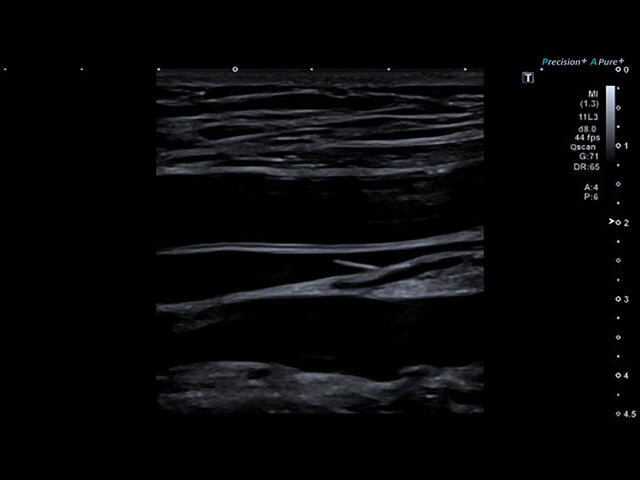

Aplio a550 – это многофункциональная УЗИ система экспертного класса. Высокое качество изображения и интуитивно понятный интерфейс поможет вам обеспечить высокую производительность и скорость проведения исследования.

Система имеет компактные размеры, удобную центральную педаль блокировки, высококонтрастный экран в диагональю 23", регулировка по высоте на расстояние более 36 см, а панель управления и монитор могут быть настроены для любого положения сканирования.

Отличная цветопередача с высокой детализацией и четкостью изображения. Устройство подходит для профессионального использования в частных кабинетах и крупных медицинских центрах. Комплектация сканера применима для самых разных исследований. Широкий диапазон прикладного клинического программного обеспечения высокоэффективен для общих исследований, сердечно-сосудистых, гинекологических, ортопедических, урологических.

Aplio a550 имеет интуитивно понятный пользовательский интерфейс, который упрощает работу во время исследований. В зависимости от режима визуализации, подсказки на экране, комментарии и индивидуальные настройки позволяют оптимизировать и ускорить рабочий процесс.

Aplio a550 может работать с линейным матричным датчиком и поддерживает новейшие монокристаллические датчики. Также Aplio a550 поддерживает большое количество дополнительных опций, таких как - SMI, Компрессионная эластография, Эластография сдвижной волны, Smart Fusion, исследования с использованием контраста (CEUS), 3D реконструкции в реальном времени (4D), функции автоматической оценки подвижности миокарда и фракции выброса.

Режимы визуализации

B-Режим

M-Режим

M-Режим - Цветной

CDI-Режим - Цветной допплер

DP-Режим - Энергетический доплер

Dir.PD-Режим - Направленный энергетический доплер